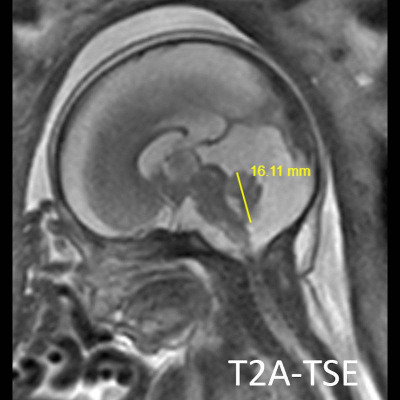

- B) Aksiyel ve sagittal T2A görüntülerde gyrus ve sulkuslarda azalma mevcut olup korteks kalınlaşmış görünümde ve operkulizasyon ayırt edilememiştir. Korteks beyaz cevher ayrımı zor seçilmektedir (ok) Ekstraaksiyel BOS mesafesi artmış görünümdedir (ok). Yapılan ölçümlerde; tegmentovermian açı :8 derece (ok) serebellar vermis boyutları kraniokaudal: 16 mm, aksiyel: 5,5×8,5 mm (ok) ölçülmüş olup BPD:27w ile uyumlu olan fetüste haftasıyla uygun olarak değerlendirilmiştir.